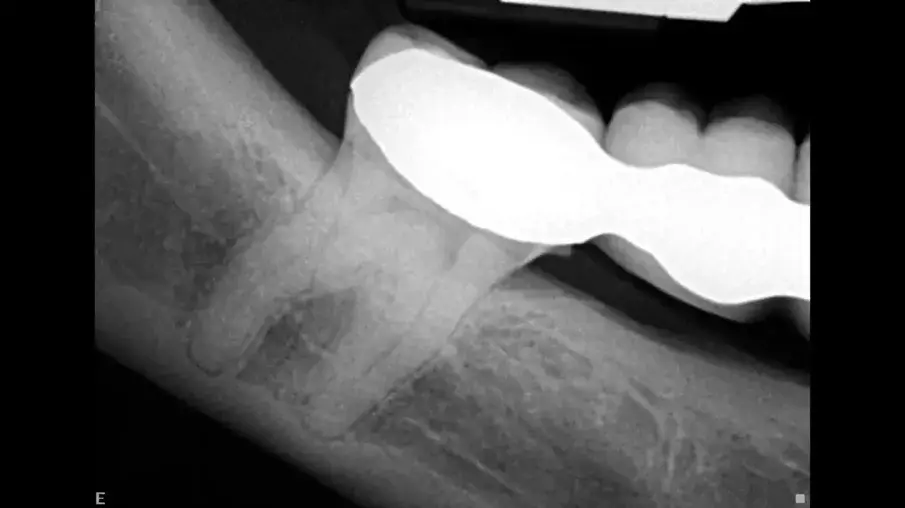

Същият пациент имаше фистула в букалната област на нивото на фуркацията на долен молар в резултат на твърде високите оклузални контакти, които не са били коригирани след поставянето на инлея на горния молар (фиг. 8). Това е довело до активиране на субстанция Р, която впоследствие е създала калцификацията в горния молар и необратимото възпаление на долния молар – ефект на микротравмата.

Фиг. 8а Предоперативна рентгенография, показваща калцирана пулпна камера и нерентгеноконтрастна лезия в областта на фуркацията (а). Фистула, насочена към коронарната част на кореновия канал (б).

Фиг. 8б Предоперативна рентгенография, на която се вижда фистулата, насочена към коронарната част на кореновия канал.